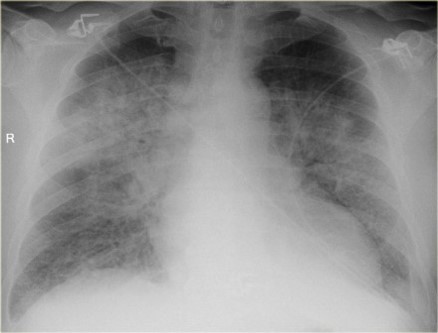

63 yo male smoker with history of dyslipidemia, HTN and myocardial infarction presents with increasing SOB of 1 week duration

View: PA

DX: CHF, diffuse pneumonia, pulmonary edema